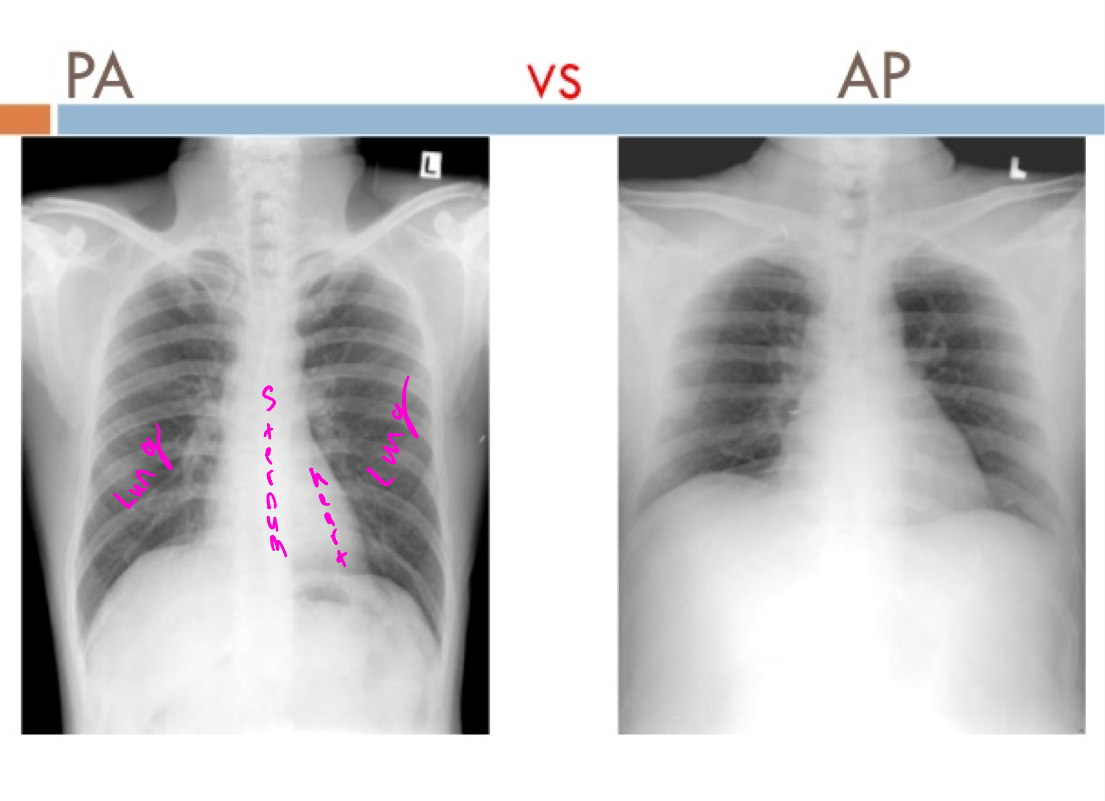

PA view

Beam goes back to front

AP view

beam goes front to back

PA vs AP

X-ray comparison